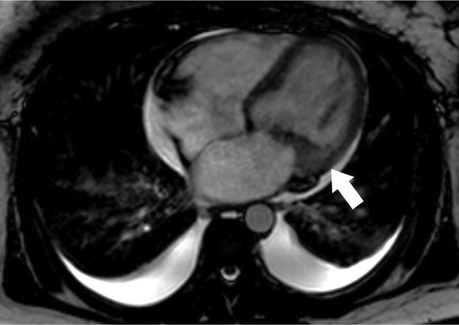

Figure 3

Libman-Sacks endocarditis on CMR. Cine 4-chamber view shows mass-like mitral valve vegetation and valve thickening (white arrow) consistent with Libman-Sacks endocarditis.